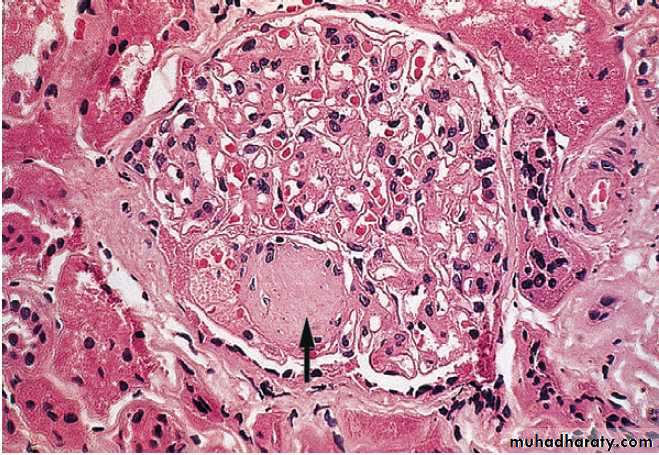

Type 1 diabetes is a T cell-mediated autoimmune disease

involving destruction of the insulin-secreting β cells in the pancreatic islets. Progressive loss of β cell function takes place over a prolonged period (months to years), classical symptoms s, occurs only when 80–90% of the functional capacity of β cells has been lost. The pathology in the pre-diabetic pancreas is characterised by ‘insulitis’ with infiltration of the islets by mononuclear cells containing activated macrophages, helper cytotoxic and suppressor T lymphocytes, natural killer cells and B lymphocytes. The destructive process is β cell specific, the glucagon and other hormone-secreting cells in the islet remaining intact.